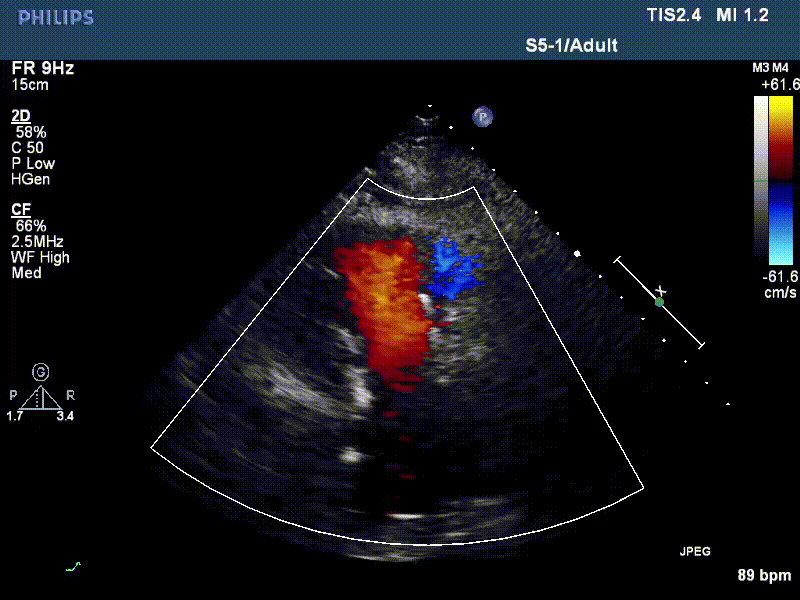

流并分別伴有房顫和房撲,高外科手術(shù)風險。術(shù)前超聲提示,兩例患者下腔靜脈寬度分別為13mm和29mm,右房內(nèi)徑(上下徑和左右徑)分別為52×41mm和53×43mm,彩色多普勒顯示極重度三尖瓣反流,VCW分別為14×15mm和10mm。

1年前,兩例患者因難治性雙下肢水腫輾轉(zhuǎn)多家醫(yī)院尋求救治,考慮到兩例患者高齡、基礎(chǔ)疾病多、STS評分高,不適合傳統(tǒng)外科開胸手術(shù),葛均波院士及其團隊周達新教授、潘文志教授、張源博士、陳莎莎博士、陳丹丹博士聯(lián)合心外科王春生、魏來主任,麻醉科繆長虹、郭克芳主任以及心超室的潘翠珍教授、李偉教授共同討論決定,采用我國創(chuàng)新器械LuX-Valve Plus經(jīng)血管三尖瓣置換系統(tǒng)為患者進行手術(shù)。相較于第一代產(chǎn)品LuX-Valve,LuX-Valve Plus經(jīng)血管三尖瓣置換系統(tǒng)對輸送系統(tǒng)進行了全面升級,實現(xiàn)了經(jīng)頸靜脈入路的方式,進一步減小了手術(shù)風險和對患者的創(chuàng)傷。目前隨訪1年心超結(jié)果顯示,三尖瓣極重度反流消失,人工三尖瓣瓣膜穩(wěn)定牢固,瓣葉活動度良好,右心室及下腔靜脈明顯縮小,心輸出量增加。兩位老人手術(shù)后沒有出現(xiàn)過胸悶氣促的癥狀,下肢水腫緩解,活動耐力提升,生活質(zhì)量也大為提高。

圖2 患者植入LuX-Valve Plus后,1年隨訪心超提示無三尖瓣反流